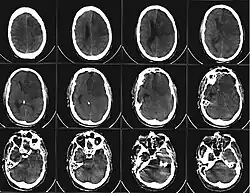

Серия КТ-снимков головного мозга, демонстрирующая ишемический инсульт в зоне кровоснабжения левых передней и средней мозговых артерий (на изображении — справа).

При остром периоде ишемического инфаркта мозга магнитно-резонансная томография (МРТ) является более эффективным методом ранней визуализации, чем компьютерная томография. На стандартных томограммах в 80 % наблюдений в первые 24 часа после развития окклюзии сосуда ишемические изменения уже становятся видимыми. При дополнительном введении контрастных препаратов в области ишемии отмечается контрастирование артериальных сосудов на Т1-взвешенных изображениях, что говорит о снижении в них скорости кровотока. Эти изменения могут развиваться уже в течение первых минут после окклюзии. Кроме того, к ранним МР-проявлениям относят изменения паренхимы мозга, выражающиеся в утолщении извилин и сужении субарахноидальных пространств на Т1-взвешенных томограммах, и повышение сигнала в режиме Т2. Эти изменения обычно выявляются не ранее чем через 8 часов после окклюзии[34]:347-348.

При компьютерной томографии (КТ) головы область гиподенсивности (пониженной плотности) у большинства больных выявляется через 12—24 ч с момента развития ишемического инсульта. При меньшей давности поражение не обнаруживается почти в половине случаев. Небольшие по размеру инфаркты мозга (инфаркты в мозговом стволе и лакунарные инфаркты) часто не дифференцируются на бесконтрастных КТ-изображениях даже на 3—4-й день заболевания (в период, когда инфаркты других локализаций визуализируются наилучшим образом), однако могут быть обнаружены при КТ с контрастированием. Проведение КТ с внутривенным контрастным усилением также показано в неясных случаях для дифференциальной диагностики[35].